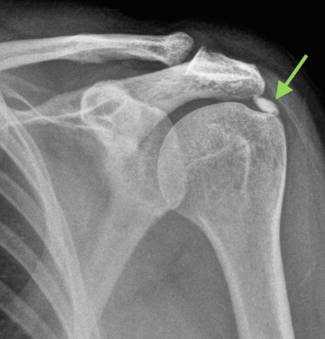

어깨 석회성건염의 진단은 간단하게 X-ray 검사 또는 초음파 검사로 진단 합니다. X-ray 검사상 큰 석회들은 어깨뼈 주변으로 하얗게 관찰 되기도 하며 미세 석회들의 경우는 X-ray 검사로 보이지 않고 초음파로 관찰 되며 이때 회전근개 힘줄에 생긴 석회의 크기나 모양을 초음파로 통해 자세하게 관찰 하며 진단 할 수 있습니다. 또한 석회성건염을 진단 할때 단순하게 회전근개 힘줄에 석회가 있는지만 파악 하는것이 아니라 회전근개의 파열 여부도 체크 해야 합니다. 석회성건염이 발생하는 원인이 앞써 말씀 드렸듯 힘줄의 노화로 인해 생기는것 인데 힘줄에 석회가 있는 경우 회전근개의 파열 이나 회전근개의 건증이 함께 관찰 되는 경우가 많기 때문에 어깨 석회성건염 진단시 회전근개 힘줄의 손상 유무도 확인하고 같이 치료가 되어야 재발 없이 석회성건염 치료가 될수 있습니다.